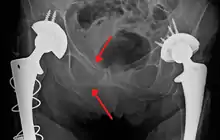

Blunt pelvic trauma

The most common causes of blunt pelvic trauma are motor vehicle crashes and multiple-story falls, and thus pelvic injuries are commonly associated with additional traumatic injuries in other locations.[27] In the pelvis specifically, the structures at risk include the pelvic bones, the proximal femur, major blood vessels such as the iliac arteries, the urinary tract, reproductive organs, and the rectum.[28][27]

.png.webp)

One of the primary concerns is the risk of pelvic fracture, which itself is associated with a myriad of complications including bleeding, damage to the urethra and bladder, and nerve damage.[29] If pelvic trauma is suspected, emergency medical services personnel may place a pelvic binder on patients to stabilize the patient's pelvis and prevent further damage to these structures while patients are transported to a hospital. During the evaluation of trauma patients in an emergency department, the stability of the pelvis is typically assessed by the healthcare provider to determine whether fracture may have occurred. Providers may then decide to order imaging such as an X-ray or CT scan to detect fractures; however, if there is concern for life-threatening bleeding, patients should receive an X-ray of the pelvis.[30] Following initial treatment of the patient, fractures may need to be treated surgically if significant, while some minor fractures may heal without requiring surgery.[27]

A life-threatening concern is hemorrhage, which may result from damage to the aorta, iliac arteries or veins in the pelvis. The majority of bleeding due to pelvic trauma is due to injury to the veins.[29] Fluid (often blood) may be detected in the pelvis via ultrasound during the FAST scan that is often performed following traumatic injuries. Should a patient appear hemodynamically unstable in the absence of obvious blood on the FAST scan, there may be concern for bleeding into the retroperitoneal space, known as retroperitoneal hematoma. Stopping the bleeding may require endovascular intervention or surgery, depending on the location and severity.[28]